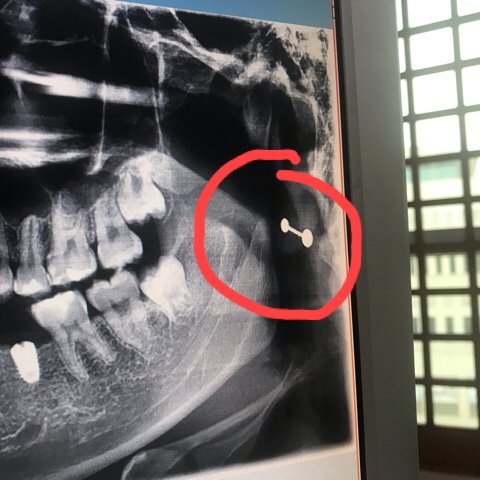

내 엑스레이 사진 볼때마다

저게 뭐지 싶었는데 생각해보니까 피어싱이였음 ㅋㅋ 개웃기다